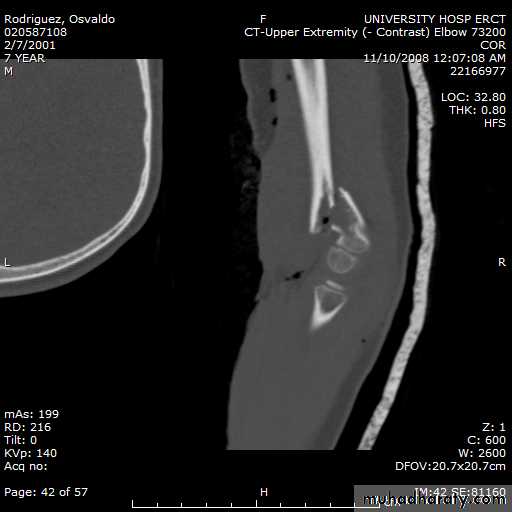

8 y.o. rolled over on an ATV

with mild closed head injuryClinical appearance

Only N-V deficit:

Anterior interosseous n. function weak

Radial A.

FCR Musc.Imaging Studies

How are we going to stabilize this boy’s fracture?